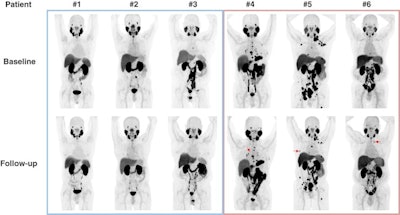

The researchers enlisted six men with mCRPC. Patients receiving bipolar androgen therapy were imaged with F-18 DCFPyL PET/CT at baseline and after three months of treatment. Progression by PSMA-targeted PET/CT was defined as the appearance of any new lesion that was avid for the F-18 DCFPyL tracer. All participants had mCRPC and prior treatment with at least one novel androgen receptor-targeted therapy.

Changes in F-18 DCFPyL-PET/CT imaging after three months of bipolar androgen therapy. Baseline and follow-up maximum intensity projection whole-body images are shown for each patient. For patients 4-6, representative new lesions or sites of progression are indicated by red arrows. Image courtesy of the Journal of Nuclear Medicine.Three of six (50%) patients had progression on F-18 DCFPyL PET/CT. All three had stable disease or better on contemporaneous conventional imaging. Radiographic progression on CT or bone scanning was observed within three months of progression on F-18 DCFPyL PET/CT.

In addition, for the three patients who did not have progression on F-18 DCFPyL-PET/CT, radiographic progression was not observed for at least six months.